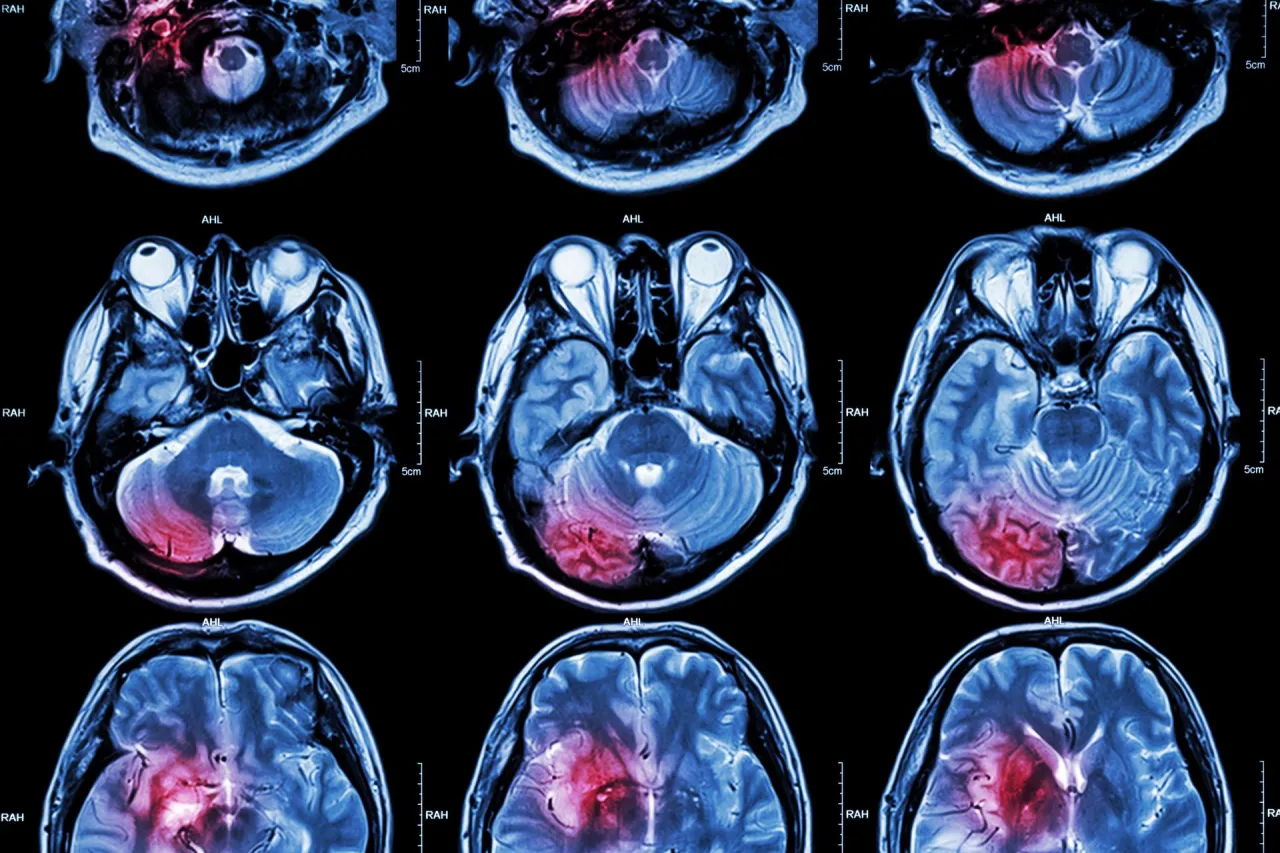

Udar mózgu jest stanem bezpośredniego zagrożenia życia i główną przyczyną trwałej niepełnosprawności.

- Udar niedokrwienny (80-87% przypadków) jest najczęstszy, udar krwotoczny (15-20%) ma wyższą śmiertelność.

Mechanizm zniszczenia, jaki zachodzi w mózgu podczas udaru, jest brutalny. W przypadku udaru niedokrwiennego, gdy dopływ krwi zostaje odcięty, komórki mózgowe, pozbawione tlenu i glukozy, zaczynają obumierać w ciągu kilku minut. Ten proces jest nieodwracalny. Podobnie dzieje się w udarze krwotocznym, gdzie wylew krwi do mózgu nie tylko uszkadza tkankę bezpośrednio, ale także zwiększa ciśnienie wewnątrzczaszkowe, uciskając i niszcząc zdrowe komórki. Każda zniszczona komórka mózgowa to utracona funkcja, która może nigdy nie zostać w pełni przywrócona.

Najczęstszym typem jest udar niedokrwienny, zwany również zawałem mózgu. Stanowi on około 80-87% wszystkich przypadków. Dochodzi do niego, gdy tętnica doprowadzająca krew do mózgu zostaje zablokowana, najczęściej przez zakrzep. Chociaż udar niedokrwienny charakteryzuje się niższą śmiertelnością niż udar krwotoczny, często prowadzi do trwałej niepełnosprawności, wymagającej długotrwałej rehabilitacji i adaptacji do zmienionych warunków życia.Znacznie groźniejszy, choć rzadszy, jest udar krwotoczny, czyli wylew. Stanowi on około 15-20% przypadków udarów. Dochodzi do niego, gdy naczynie krwionośne w mózgu pęka, powodując krwotok. Ten typ udaru wiąże się z wyższą śmiertelnością i cięższym przebiegiem. Statystyki pokazują, że połowa pacjentów z udarem krwotocznym umiera w ciągu pierwszych dwóch dni od zdarzenia, co czyni rokowania znacznie poważniejszymi i podkreśla jego dramatyczny charakter.